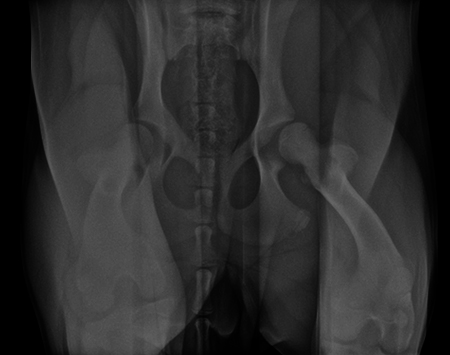

A 5-month-old spayed female labrador retriever puppy weighing 22.0 kg presented with bilateral hind limb weakness and a bunny-hopping gait in the hind limbs. Physical examination revealed bilateral hip instability (positive Ortolani sign) and mild pain on full extension of the hips. Slight crepitus was palpated in the left hip. The gluteal muscles appeared to have mild atrophy. The neurological exam was normal. Radiographic examinations revealed bilateral hip subluxation and a distraction index of 0.5 of the right hip and 0.7 of the left hip (Fig 3). No evidence of osteoarthritis was observed.

A diagnosis of juvenile hip dysplasia was made. The right hip was considered an acceptable candidate for double pelvic osteotomy (DPO; note that in a 5-month-old dog, an osteotomy of the pubis (as performed in a TPO) is not necessary due to the bony compliance at this young age). The left hip conformation was considered too abnormal for a corrective osteotomy and was not treated. The owner was counseled that a total hip replacement (THR) may be needed in the future on the left hip.